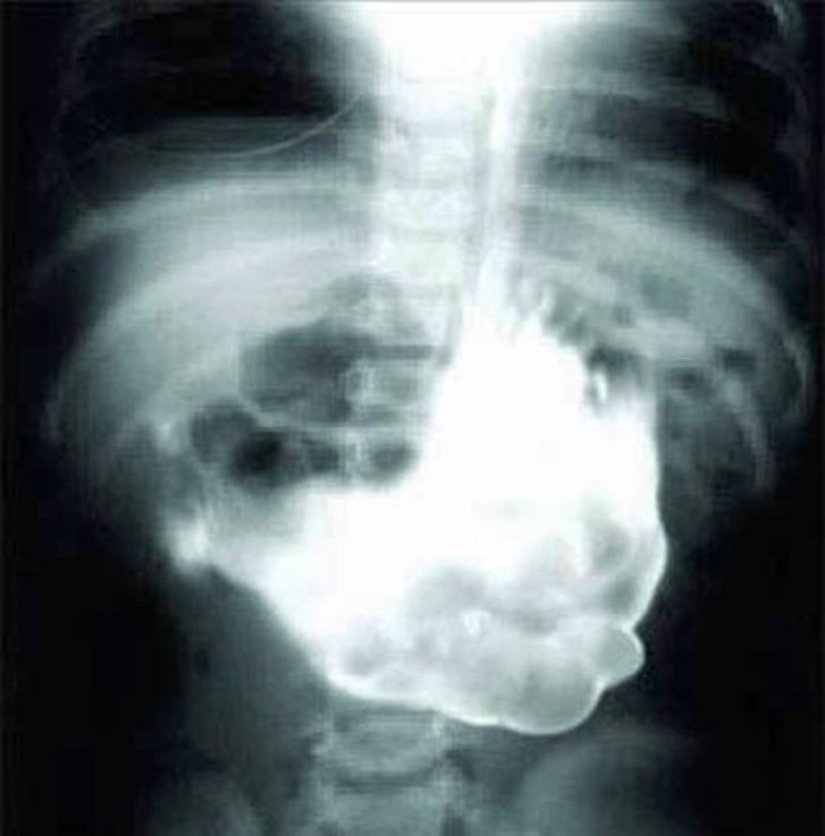

17. A huge ball of wool.